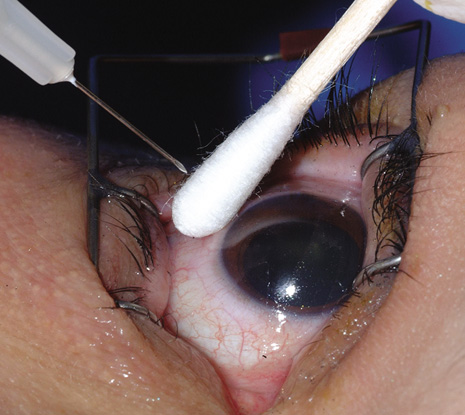

An alternative method involves direct inoculation of the initially aspirated vitrectomy specimen into standard blood culture bottles (Fig. 2).37 This latter technique is particularly useful at night or on the weekend when the microbiology laboratory staff are not available to assist in the processing of the vitrectomy specimen. In a retrospective review of 83 cases, this blood culture bottle method for processing vitrectomy specimens yielded a 91% incidence of positive culture results.37 This rate of positive culture results from clinically diagnosed endophthalmitis cases was similar to simultaneously processed specimens using the membrane filter system.

Fig. 2. Blood culture bottles may be used for vitrectomy specimens at night or on the weekend when the microbiology staff are not available. Left: The bottle is unopened and has clear media. Right: The inoculated bottle shows growth of organisms as manifested by the opaque media.